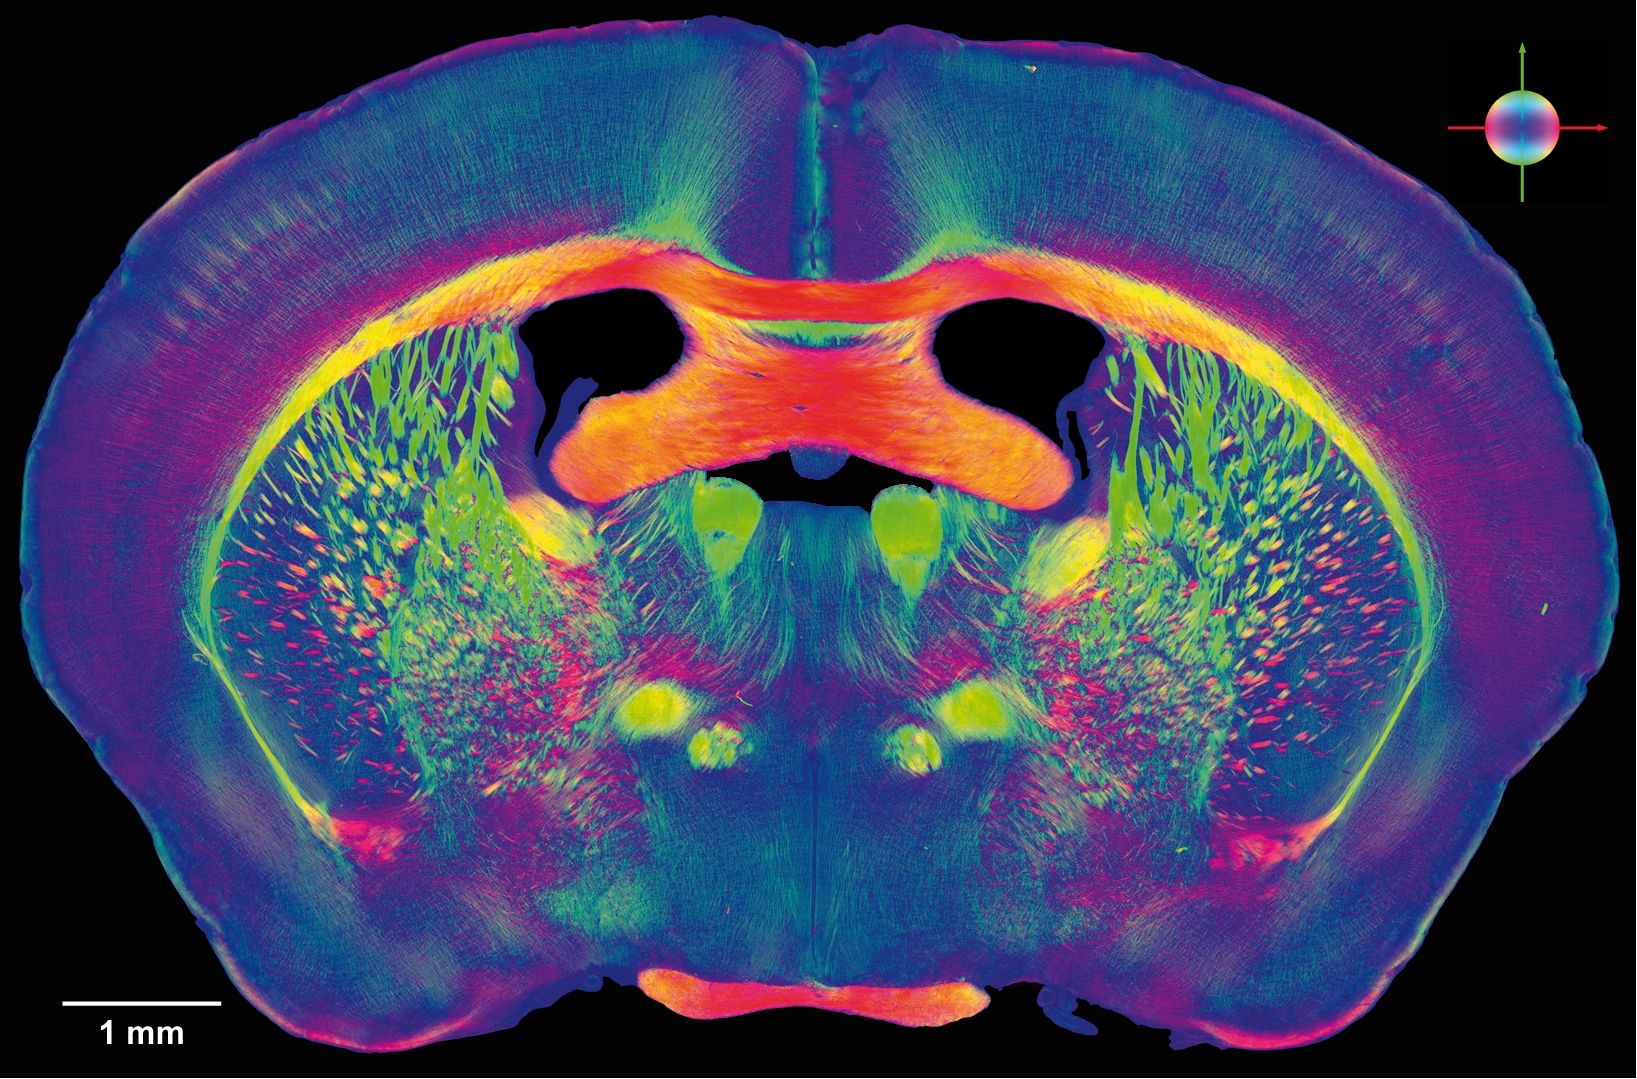

脳の85%は大脳。脳の前部は左右二つの半球から成り、繊維の厚い帯でつながっている。この部分は知的機能、感情、人格に関わる。

脳の40%は樹状突起および軸索突起(神経細胞から糸のように伸びていて、細胞体から細胞体へと神経インパルスを伝導する)であり、60%がニューロン(脳神経細胞)である。

ニューロンの数は約1千億個。

ニューロン1個につき1千〜1万個のシナプス(ニューロン間の接合部)がある。

マークラム氏と連邦工科大学ローザンヌ校のチームは8年前から、マウスの脳の切片を用いて、このようなリバース・エンジニアリングと予測神経科学の手法を検証する「ブルー・ブレイン・プロジェクト」に取り組んできた。

研究所では、最先端のIBMのブルー・ジーン・スーパーコンピューターが休みなくデータを処理し続けている。相互に結びついたマウスの皮質柱100本の電気活動のシミュレーション・モデルを構築するためだ。マウスの皮質柱1本には3万個のニューロンが存在する。しかし、人間の脳にはニューロンが860億個あるのだ。